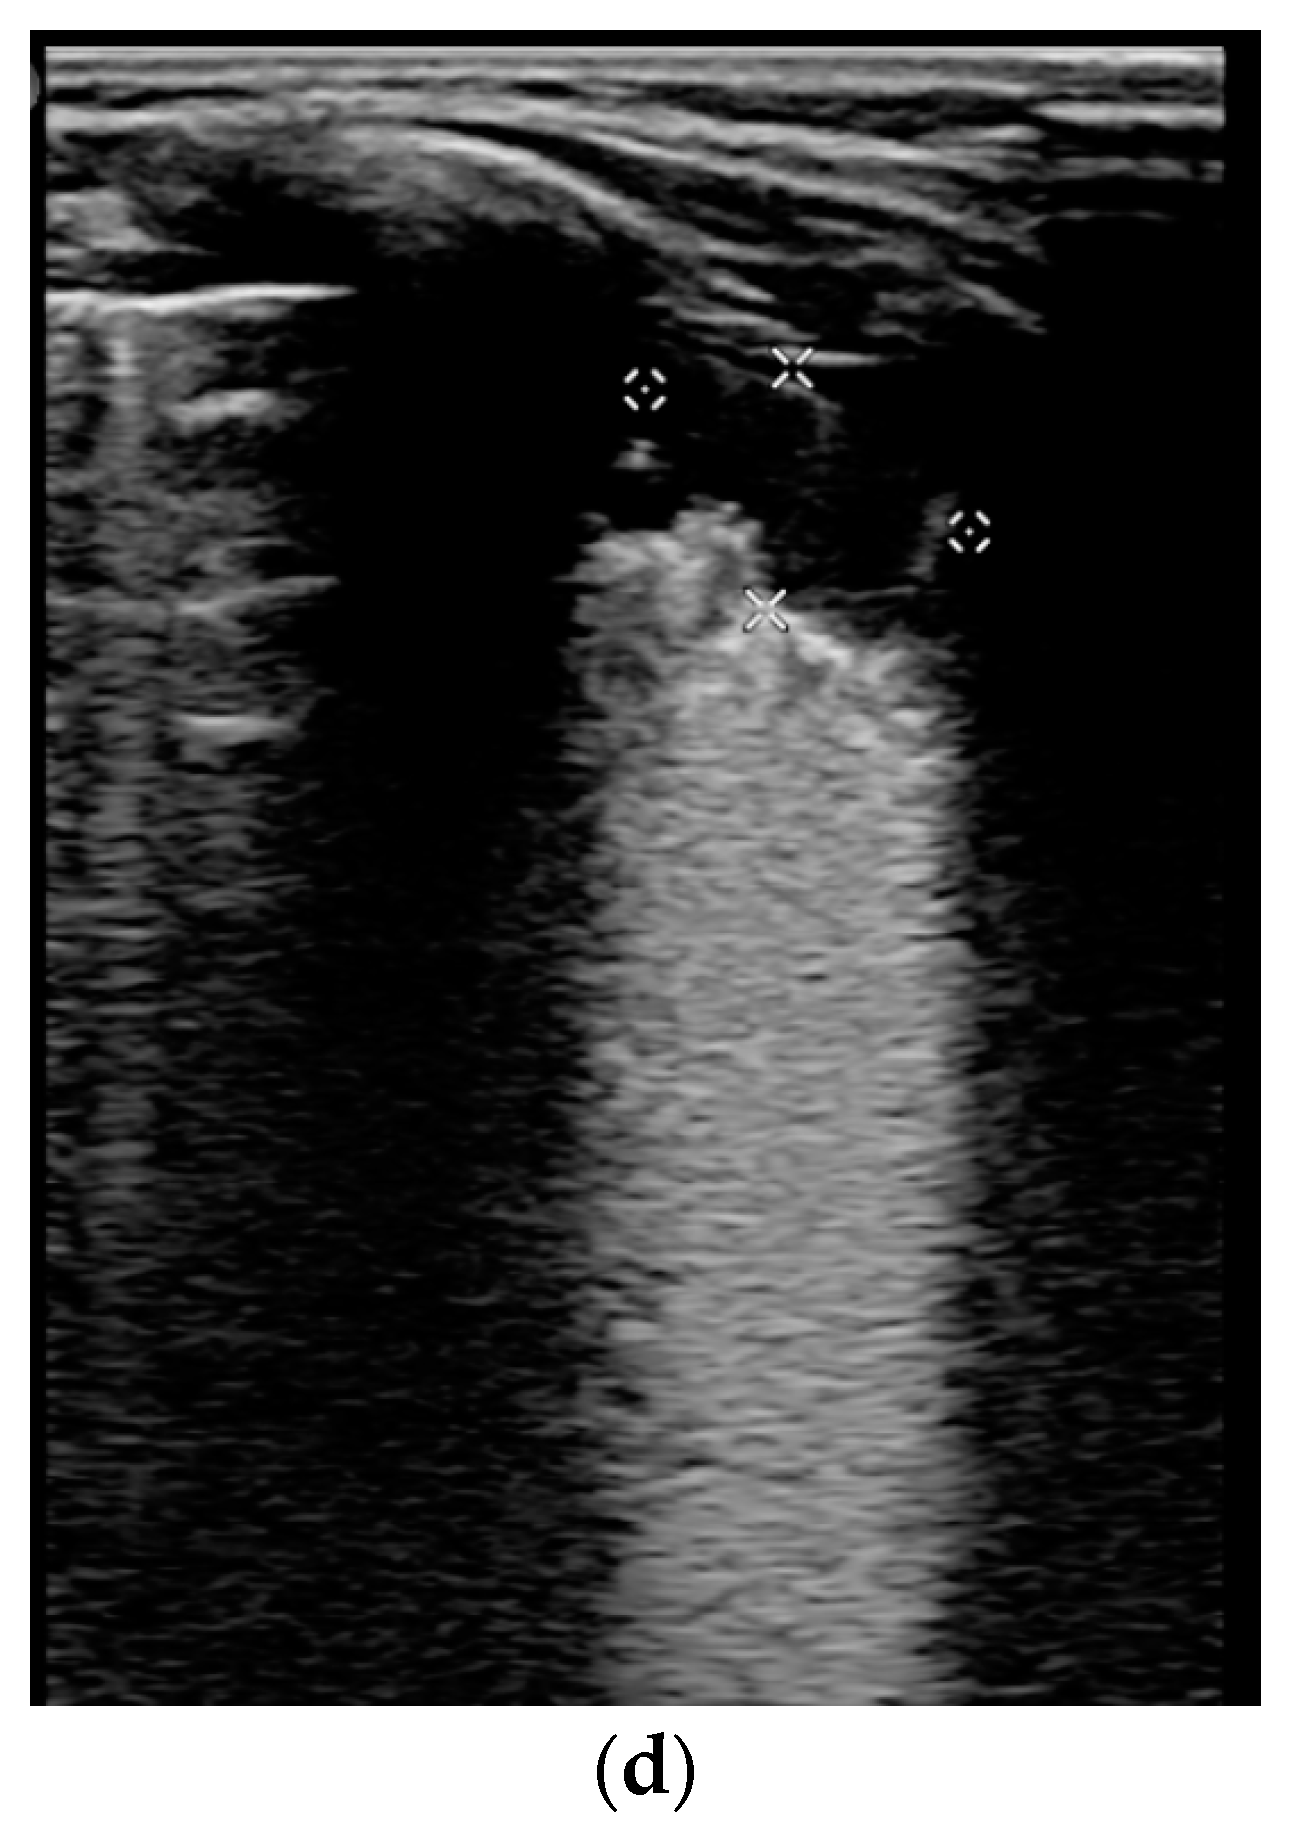

- Transverse physiologic A-lines that depict healthy parenchyma;

- Isolated/sparse vertical B-lines are equivalent to interstitial edema;

- Confluent vertical B-lines correspond to alveolar edema;

- Subpleural/peripheral consolidations;

| LUSS = 0 Points | LUSS = 1 Point | LUSS = 2 Points | LUSS = 3 Points |

|---|---|---|---|

| Normal/physiological A-lines | More than 2 B-lines (sparse B-lines) with associated pleural abnormalities | Coalescent or confluent B-lines | Large peripheral consolidation (wider than 1 cm) in association or not with air bronchogram |

| One or two B-lines per intercostal space | ‘White-lung’ aspect or small peripheral consolidation (smaller than 1 cm) |